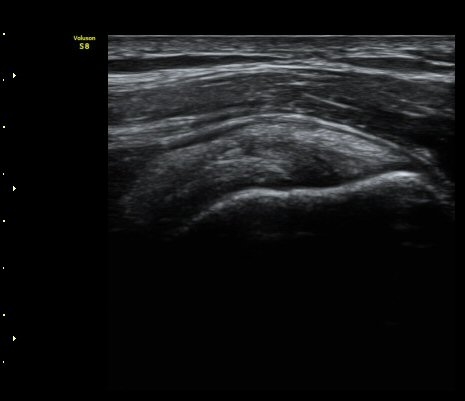

°ßºÀ¿À±¸µ¹±âÀδë Á¾´Ü¸é°Ë»ç¿¡¼­ ÀδëÀÇ ¿ÜÃø¿¡ ±¹¼ÒÀûÀÎ ÀÎ?ºñÈİ¡ °üÂûµÈ´Ù(»çÁø 3).

±Ø»ó°Ç Á¾´Ü¸é°Ë»ç½Ã ±Ø»ó°ÇÀÇ Ç¥Ãþ¿¡¼­ °üÂûµÇ´Â °ßºÀ¿À±¸µ¹±â Ⱦ´Ü¸é°Ë»ç»ó¿¡¼­

ÀδëÀÇ ºñÈİ¡ °üÂûµÈ´Ù(»çÁø 4). ±Ø»ê°ÇÀÇ Á¾´Ü¸é°Ë»ç¿Í Ⱦ´Ü¸é°Ë»ç¿¡¼­ ±Ø»ê°Ç ½ÉÃþ¿¡